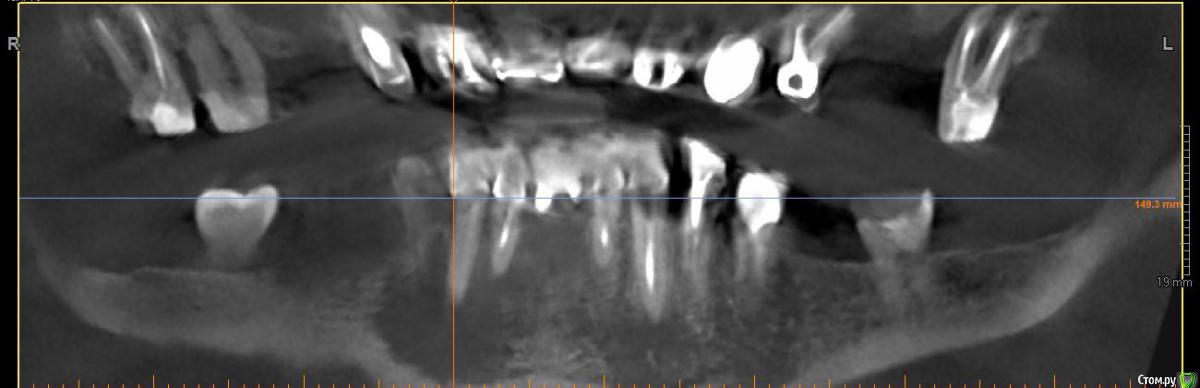

Evikrol Опубликовано 14 октября, 2015 Поделиться Опубликовано 14 октября, 2015 (изменено) Под мостовидным протезом нашли кисту. Хотим сохранить конструкцию перелечив 43 через коронку, ну и 44 тоже. А так же хотим вскрыть вестибулярную стенку кисты, провести кюретаж, промыть хлоргексидином. Дренаж ставить, нет? И вообще какой протокол правильный? Изменено 14 октября, 2015 пользователем Evikrol Ссылка на комментарий

Fibez Опубликовано 15 октября, 2015 Поделиться Опубликовано 15 октября, 2015 согласен с предыдущими советами. Кстати, КТ не информативно у Вас. Не видно нормально ничего вообще 1 Ссылка на комментарий

Evikrol Опубликовано 15 октября, 2015 Автор Поделиться Опубликовано 15 октября, 2015 Поступил в гос с отёком нижней челюсти справа. Хирург сделал разрез, поставил дренаж. На прицельном сперва ничего не поняли, на кт видно что в очаг деструкции вовлечены три зуба. Сейчас уже в нашей клинике проводим эндо 43,44 и планировали провести кюретаж полости кисты. Думаете не надо?Да на кт не чётко видно границы очага, это самый информативный срез. Ссылка на комментарий

DoctorT Опубликовано 16 октября, 2015 Поделиться Опубликовано 16 октября, 2015 Не боитесь, что челюсть сломаете при такой то кисте? Кортикалка расплавлена. Мост снять, подвижность зубов оценить. Перелечить. Кисту оперировать и заполнить костнозамещим материалам. Все это под вопросом тк КТ не информативно. Ссылка на комментарий